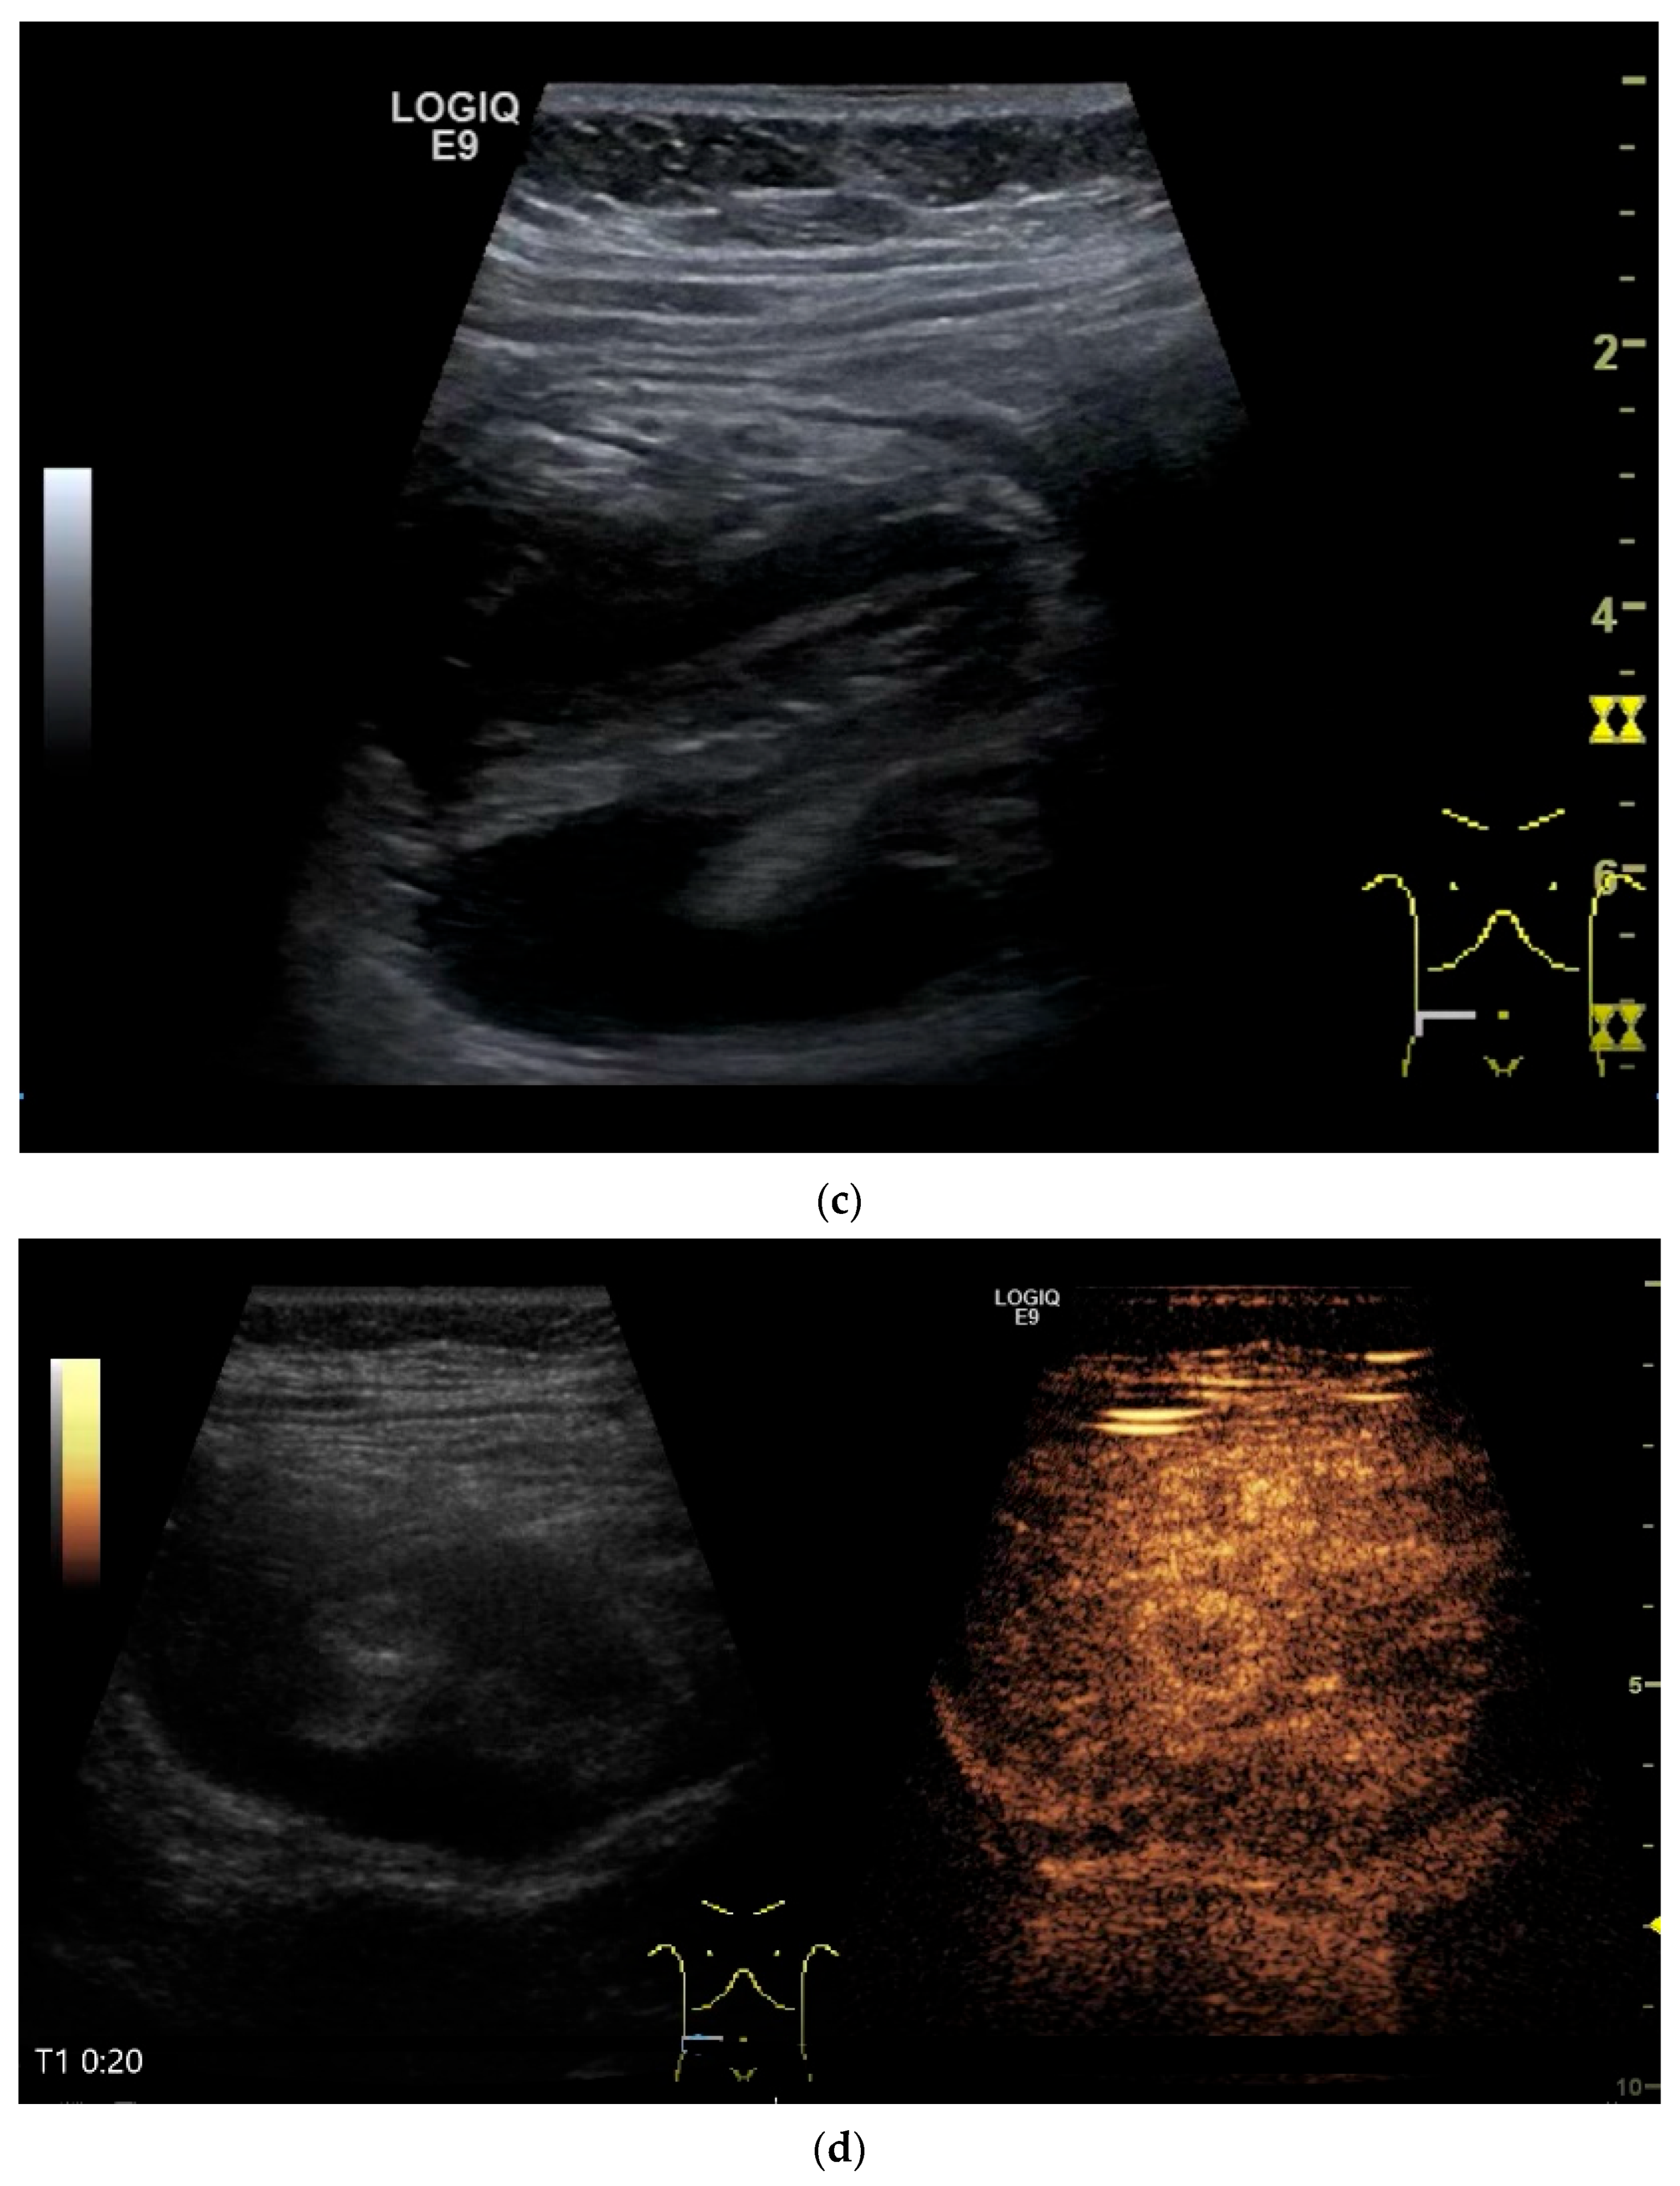

Figure 10.

Diffuse large B-cell lymphoma (DLBCL). In the right mid-lower abdomen, a large, smoothly circumscribed mass is present around the ileum (“pseudo kidney sign” (a)). Using a high-resolution linear transducer, the mass appears smoothly circumscribed and almost anechoic (b). The ileum runs centrally, and the echogenic wall is clearly defined (c). This wall does not merge into the mass. Since the mass is almost anechoic, it is also difficult in different transducer positions to distinguish whether it is a liquid lesion or a solid mass (b,c). CEUS with 2.4 mL SonoVue (9 MHz linear transducer) shows homogeneous arterial enhancement (d), but the intensity decreases with time in the venous phase (e). The ileal wall enhancement centrally within the mass is more intense than that of the tumor (d,e).